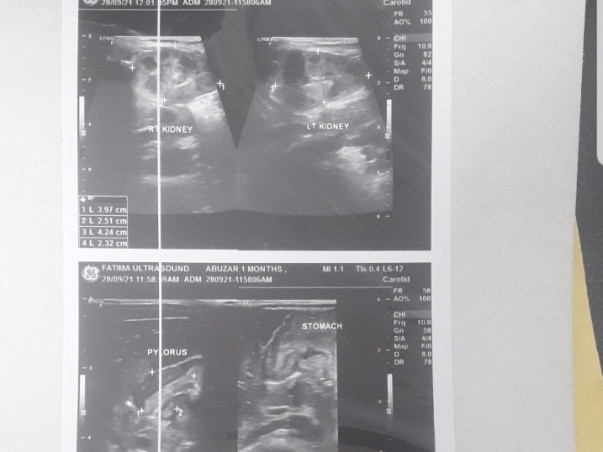

Support Master Abuzar, a 1-month-old and is suffering from pyloric stenosis it's a condition in which the opening between the stomach and small intestine thickens and it blocks the entry of food into the small intestine and it can lead to death if proper treatment is not given.